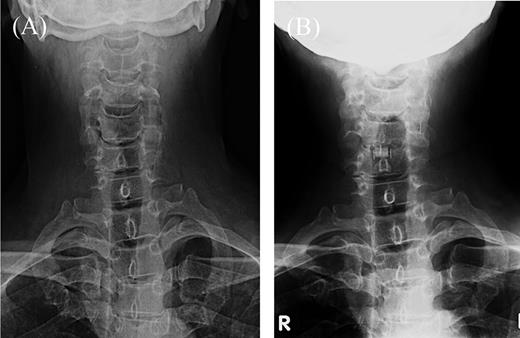

A 60-year-old man presented with 3 months of progressive pain in the right axilla and posteromedial upper extremity. He had undergone C5–6 anterior fusion for cervical spondylosis 5 years prior (Fig. 1B). He had returned to his job as a taxi driver after the anterior fusion. He did not have any traumatic injury or traffic accidents after his anterior fusion. His numerical pain scale rating was 10/10. Examination revealed no sensory disturbance, no abnormal tendon-jerk reflexes and progression of muscle weakness. Cervicothoracic scoliosis had been diagnosed before his anterior cervical fusion (Fig. 1A). Roentgenograms showed scoliosis with a right cervicothoracic curvature with a Cobb angle of 17 degrees before his anterior fusion (Fig. 1A) and 19 degrees on referral to our hospital (Fig. 1B). In addition, computed tomography (CT) scanning revealed bone spurs of the C6–7 facets (Fig. 2F). Magnetic resonance (MR) imaging showed a decrease in intervertebral height, but the nerve root canal was preserved at the C6–7 level. CT images also showed osteophytes of the superior costal facet and articular process at the T2–3 level (Fig. 2B–D). MR images demonstrated a protruded disc at the T2–3 level (Fig. 2E and F).

Roentgenograms of C5–6 anterior fusion and scoliosis of the cervicothoracic spine. (A) Cervical frontal view before anterior fusion. (B) Cervical frontal view 5 years after anterior fusion. R: right.